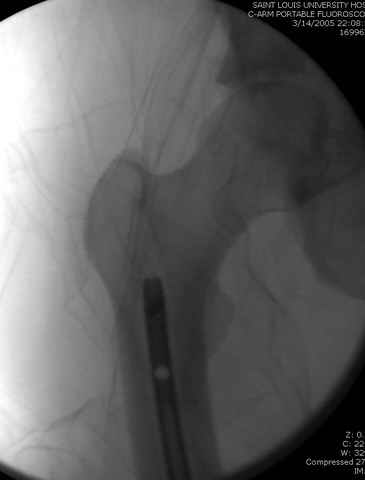

33 yo male motocross rider crashed after a jump sustaining isolated bilateral femur fxs, R side with a basicervical femoral neck and ipsilateral mid-distal 1/3 shaft, L side with a subtroch/prox 1/3 femur fx. Pt was HD stable, no LOC, GCS - 15, No other injuries, spines cleared.

Supine position on a radiolucent table.

Temporary (k-wire/guidewire) fixation in the neck if it can be anatomically reduced closed, open if necessary.

Retrograde nail right femur being careful that you don't knock off the neck fx.

DHS with de-rotation screw for neck (make sure you carefully tap the screw path so as not to spin off the reduction when the screw purchases, possible

even with a derotation screw) and use a plate that overlaps your nail (can put plate screws around nail, or through a locking hole). Alternatively, the synthes locking proximal femoral plate could be used.

Left side- same table/postion, antegrade nail

Sequence ­ Right neck, right shaft, then left shaft.

2 positions ­ 2 drapes/preps, rolled oblique for both.

Implants ­ plenty of opinions exist for the right side...some would use neck screws anteriorly after reduction, then with a slender reamed locked nail

pushed in behind the neck screws for the shaft... some will advocate a recon nail for both...some will use a sliding screw for the neck then a retrograde shaft nail...some would use the sliding neck screw and a shaft plate also...lots of options.

I prefer excellent neck reduction either closed or open, screws high and low anteriorly for it, then a frail locked nail slipped in behind the neck screws for the shaft.

Some will also advocate hip capsulotomy as well to relieve capsular pressure related issues... it¹s done when you choose ORIF of the neck.

i would use fx table with 2 preps/drapes

after perfect reduction (either closed or open) i would attempt 1 implant to treat both (i.e. TFN or Intertan). can do anything though like Dr. Routt mentioned. intertan is nice because of the rotational stability it imparts in the neck